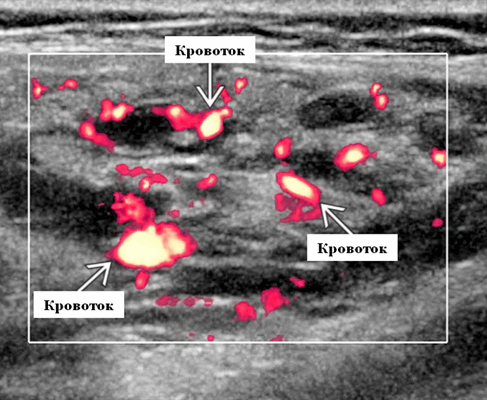

Импульсный допплер. Лоцируются артериальные и венозные волны. Средняя пиковая скорость венозной крови не повышена (повышена при истинной артериовенозной мальформации). Индекс резистентности зависит от фазы, увеличивается при лечении пропранололом (0,4-0,8)

Энергетический допплер. Отмеченный доплеровский сигнал потока на всем протяжении пораженных сосудов